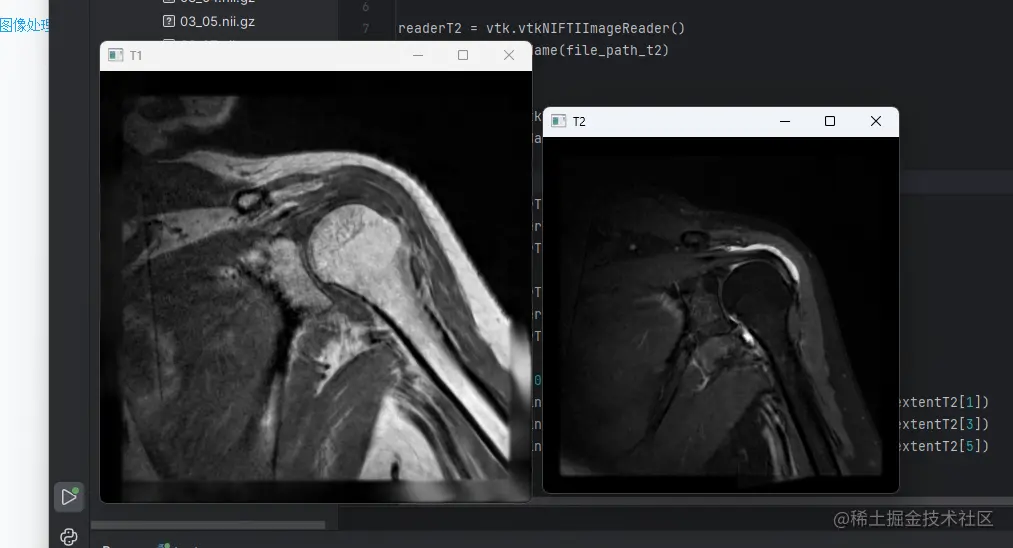

话不多说先看结果! image.png

cv2.imshow("T1",arrayT1)

cv2.imshow("T2",arrayT2)